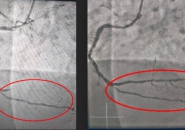

NGƯỜI PHỤ NỮ SUÝT CHẾT VÌ BỆNH NHỒI MÁU CƠ TIM

Người phụ nữ bị nhồi máu cơ tim cấp, 50 tuổi ngưng tim, ngưng thở, nhờ can thiệp kịp thời đã thoát cửa tử.